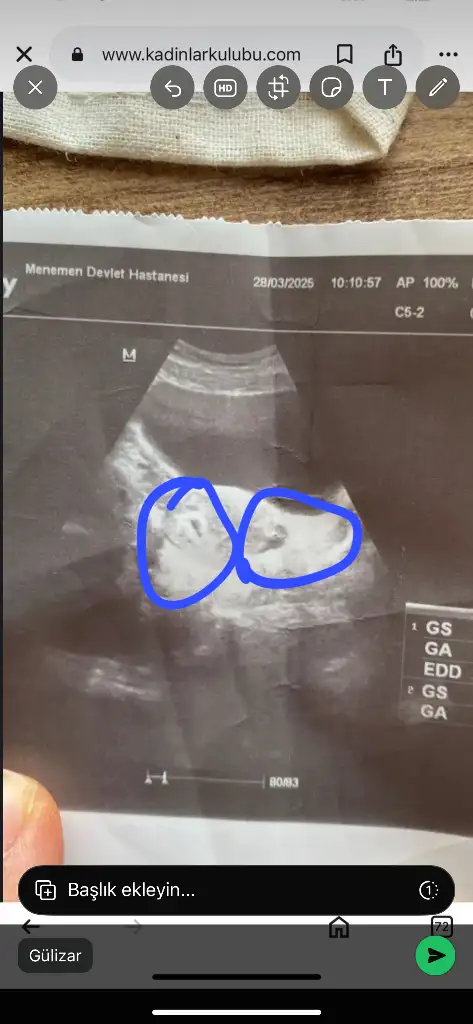

İnanın ultrasyon boş hiç birşey yok şaşırdım bende bilen birine attım keseyi zor gördü 😅 devlet olunca önemsemiyorlar babacım bizleri

Bak iki kese ikizler 👯 yolda ama diğeri daha küçük inşallah zamanla kapanır o fark yeter ki sağlıcakla büyüsünler

Ay valla ne bilim ben anlayamadım senin dediğin gibi gözüküyorda neden böyle çekmiş doktor neden yakınlaştırmamış acaba devlet farkı gerçekten ya

Ultrason eski olabilir onun için ama belli iki kese var